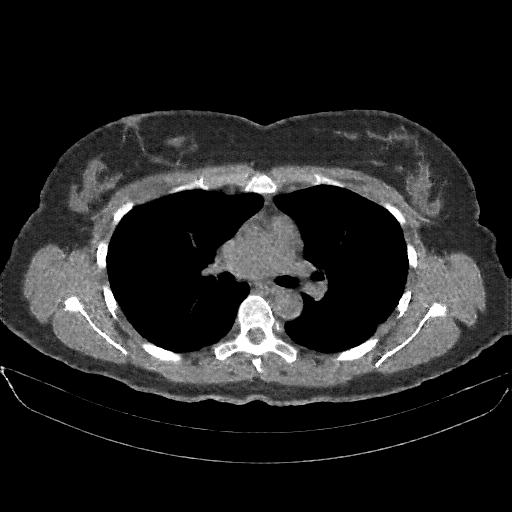

Original VENOUS CT scan

Full window (WL 1023.5, WW 4095 β†’ Low βˆ’1024, High +3071)

Actual HU range: [-1024.0, 1298.0]

Lung window (WL -600, WW 1500 β†’ Low βˆ’1350, High +150)

Actual HU range: [-1024.0, 150.0]

Mediastinum window (WL 40, WW 400 β†’ Low βˆ’160, High +240)

Actual HU range: [-160.0, 240.0]